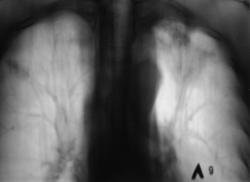

Пациент находится на диспансерном учете в туб. кабинете, по поводу инфильтративного туберкулёза верхней доли левого лёгкого, получает специфическое лечение. Пациент направлен в рентгеновский кабинет для рентгенологического исследования исследования органов грудной полости "в динамике". Проведено стандартное исследование.

Для сравнения приводятся изображения, произведенные чуть больше года тому.